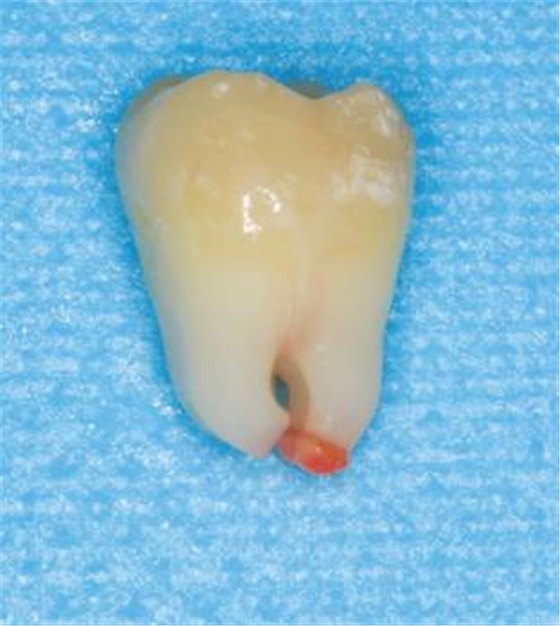

20世紀(jì)60年代,凱澤(Kaiser)首先采用根尖誘導(dǎo)成形術(shù)(apexification)治療年輕恒牙牙髓根尖周病,即在控制感染的基礎(chǔ)上,用氫氧化鈣等藥物保存根尖部牙髓或使根尖周組織沉積硬組織,促使牙根繼續(xù)發(fā)育和根尖形成。然而,藥物在根管內(nèi)的占位使患牙失去牙髓再生和向根管內(nèi)生長的機(jī)會(huì),且根管內(nèi)長時(shí)間封入氫氧化鈣將使牙根脆性增加,導(dǎo)致根折等并發(fā)癥。MTA可在未發(fā)育完全的根尖區(qū)形成人工屏障,顯著縮短年輕恒牙牙髓壞死后的療程,但這種方法不能促進(jìn)牙根發(fā)育,仍存在牙根短、根管壁薄等缺點(diǎn),遠(yuǎn)期療效欠佳。 2001年,伊瓦亞(Iwaya)等治療一例年輕恒牙慢性根尖周炎病例時(shí),在根管內(nèi)放置抗菌藥物進(jìn)行徹底消毒,刺激根尖出血并充盈根管,冠部采用MTA嚴(yán)密封閉。隨訪30個(gè)月后,該患牙牙根繼續(xù)發(fā)育,根管壁增厚,根尖閉合,電活力測(cè)試出現(xiàn)陽性結(jié)果。隨后,陸續(xù)有學(xué)者采用此方法得到類似結(jié)果。這種通過促進(jìn)根管內(nèi)血管再生治療根尖周炎的方法稱為牙髓血運(yùn)重建(pulp revascularization)。 牙髓血運(yùn)重建的種子細(xì)胞來源主要為牙髓干細(xì)胞、根尖乳頭干細(xì)胞、牙周膜干細(xì)胞和骨髓間充質(zhì)干細(xì)胞。這些干細(xì)胞在信號(hào)分子、蓋髓劑三氧化物礦物聚合物(MTA)等誘導(dǎo)下?lián)碛胁煌姆只瘽撃?,可以形成牙髓、牙本質(zhì)和牙周韌帶。在牙根發(fā)育過程中,牙胚冠向生長,上皮根鞘誘導(dǎo)其內(nèi)側(cè)的外胚間充質(zhì)細(xì)胞(牙乳頭細(xì)胞)分化為成牙本質(zhì)細(xì)胞,形成根部牙本質(zhì),使牙根發(fā)育。牙萌出后,牙根依賴牙髓組織、根尖端牙乳頭和根尖周組織中的上皮根鞘繼續(xù)發(fā)育。 圖1 年輕恒牙根尖乳頭組織 因此,未發(fā)育完全的年輕恒牙根尖孔粗大,根尖乳頭組織(圖1)中干細(xì)胞豐富且活力較強(qiáng),還可以從周圍組織中獲得豐富的血液供應(yīng),被認(rèn)為是牙髓壞死和經(jīng)過牙髓治療后的年輕恒牙牙根得以繼續(xù)發(fā)育的主要種子細(xì)胞。因此,牙髓血運(yùn)重建和根尖誘導(dǎo)成形術(shù)都要求盡可能保守地處理患牙根管,僅使用藥物沖洗根管,盡量少或者不探查根管及機(jī)械預(yù)備,保留殘留牙髓和根尖乳頭,以保存牙髓干細(xì)胞和根尖乳頭干細(xì)胞。 無菌環(huán)境的重要性 髓腔內(nèi)細(xì)菌可以形成微膿腫阻礙血管的形成,甚至導(dǎo)致牙根炎性吸收,很難有新組織的再生,且缺少有活力的牙髓干細(xì)胞,因此感染狀況下的牙髓再生被認(rèn)為是不可能的。脫位牙牙髓因外傷致根尖血管和神經(jīng)撕脫斷裂,但未受到明顯的感染,牙髓繼續(xù)保留在根管內(nèi),通過血運(yùn)重建得以恢復(fù)活力。由此可見,無菌環(huán)境是實(shí)現(xiàn)牙髓血運(yùn)重建的一個(gè)必備條件。在無污染的情況下,建立一個(gè)根管系統(tǒng)的血流通道,可使牙髓壞死伴發(fā)根尖周炎的年輕恒牙根管內(nèi)牙本質(zhì)繼續(xù)生成,進(jìn)而促使根尖孔閉合和牙根長度增加。對(duì)于感染根管,要達(dá)到徹底的無菌則需要各種化學(xué)消毒藥物的有效搭配及應(yīng)用。根管沖洗液及根管消毒藥物的使用在牙髓血運(yùn)重建術(shù)中起到重要作用。 根管沖洗劑的影響 牙髓血運(yùn)重建技術(shù)所采用的根管沖洗劑主要包括乙二胺四乙酸(EDTA)、2.5%~6.0%次氯酸鈉(NaOCl)、氯己定(CHX)、3%過氧化氫溶液(H2O2)和生理鹽水等,這些沖洗液不僅可使根管達(dá)到無菌狀態(tài),同時(shí)對(duì)血運(yùn)重建過程產(chǎn)生不同影響。EDTA和次氯酸鈉可暴露牙本質(zhì)中的膠原纖維,增強(qiáng)宿主細(xì)胞在牙本質(zhì)上的生長,而且EDTA能夠有效地溶解牙本質(zhì)使其釋放生長因子,對(duì)牙髓血運(yùn)重建具有促進(jìn)作用。氯己定具有一定的細(xì)胞毒性,使用后需經(jīng)無菌生理鹽水再次沖洗,以免影響細(xì)胞生長。 根管消毒藥物的影響 1.三聯(lián)抗菌糊劑(TAP):感染根管內(nèi)細(xì)菌種類繁多,包括需氧菌、兼性厭氧菌和專性厭氧菌等。根管感染的復(fù)雜性意味著單一的抗菌劑不能使根管達(dá)到無菌狀態(tài),必須聯(lián)合使用抗生素。早在1996年,霍欣諾(Hoshino)等人發(fā)現(xiàn)聯(lián)合應(yīng)用由甲硝唑、環(huán)丙沙星和米諾環(huán)素組成的三聯(lián)抗菌糊劑能使根管長時(shí)間保持無菌狀態(tài),較單一使用其中任一種抗生素具備更強(qiáng)的滅菌作用。近年,隨著牙髓血運(yùn)重建技術(shù)日益受到重視,無菌環(huán)境及組織修復(fù)成為眾多學(xué)者探索的方向,三聯(lián)抗菌糊劑作為根管內(nèi)消毒藥物逐漸引起重視。動(dòng)物實(shí)驗(yàn)證明,根管內(nèi)使用0.02mg/L的三聯(lián)抗生素糊劑消毒,可以減少99%以上的菌落形成單位,大約75%經(jīng)過消毒的根管內(nèi)無細(xì)菌定植。應(yīng)用三聯(lián)抗菌糊劑進(jìn)行消毒的年輕恒牙,其根尖陰影的消退、根管壁厚度增加率和根尖發(fā)育程度明顯高于采用氫氧化鈣或甲醛甲酚消毒的患牙。 三聯(lián)抗菌糊劑對(duì)組織刺激性小,具有良好的生物相容性,目前多數(shù)研究未發(fā)現(xiàn)其對(duì)牙本質(zhì)機(jī)械性能、牙髓和根尖乳頭干細(xì)胞的生長分化或根尖周圍組織細(xì)胞的生長代謝有顯著不利影響。但亦有學(xué)者猜測(cè)其對(duì)組織存在一定的細(xì)胞毒性,因?yàn)闆]有使用三聯(lián)抗菌糊劑的動(dòng)物中觀察到了生活的牙髓組織,而使用三聯(lián)抗菌糊劑的未發(fā)現(xiàn)活髓組織。 三聯(lián)抗菌糊劑可能出現(xiàn)細(xì)菌耐藥性是這種高效消毒藥物存在的缺點(diǎn)之一,而米諾環(huán)素引起牙齒內(nèi)染色的問題是其另一主要缺陷。學(xué)者建議以下方法解決牙齒染色問題:①用頭孢克洛代替米諾環(huán)素;②使用牙本質(zhì)粘接劑及復(fù)合樹脂隔絕米諾環(huán)素與牙齒冠部的接觸;③使用傳遞器械將TAP導(dǎo)入釉牙骨質(zhì)界(CEJ)根方;④采用過硼酸鈉(sodium perborate)進(jìn)行內(nèi)漂白。 2.氫氧化鈣:氫氧化鈣作為傳統(tǒng)的根管消毒藥物,具有較強(qiáng)的滅菌能力,能使根管內(nèi)保持無菌狀態(tài)。牙髓血運(yùn)重建治療年輕恒牙牙髓根尖周病的臨床病例報(bào)告中,部分采用氫氧化鈣作為根管內(nèi)消毒藥物及蓋髓劑亦取得一定的療效,顯示氫氧化鈣在牙髓血運(yùn)重建中具有良好的促進(jìn)作用。然而,根管內(nèi)長期使用氫氧化鈣可能改變牙本質(zhì)的機(jī)械性能,提高牙根折斷的風(fēng)險(xiǎn);可使根管中形成鈣化屏障,阻礙牙髓組織的生長;可能殺死剩余牙髓組織的干細(xì)胞,損傷上皮根鞘和根尖乳頭及其中的干細(xì)胞,使其失去誘導(dǎo)周圍未分化的細(xì)胞分化為成牙本質(zhì)細(xì)胞的能力。研究發(fā)現(xiàn),氫氧化鈣僅充填至冠1/2者,牙根厚度增加率從52%提高至55%,推測(cè)原因是氫氧化鈣未與根尖乳頭細(xì)胞接觸,避免了其細(xì)胞毒性的影響。 單純根管腔道并不能促進(jìn)根尖新生組織向根管內(nèi)生長,需要支架以引導(dǎo)組織生長。合適的支架應(yīng)具備能促進(jìn)細(xì)胞生長和分化、選擇性黏附凝集細(xì)胞、包含生長因子和生物降解性等條件,其中應(yīng)用較多的是自身血凝塊及富含血小板血漿。 自身血凝塊 誘導(dǎo)根尖組織出血形成血凝塊作為蛋白組織支架是目前牙髓血運(yùn)重建中的主要方法。血凝塊不僅可以使細(xì)胞表面整合因子與纖維塊產(chǎn)生黏附,選擇性吸附細(xì)胞,還包含豐富的生長因子,促使細(xì)胞生長分化。血小板分泌的生長因子包括血小板衍生生長因子(PDGF)、轉(zhuǎn)化生長因子β1(TGF-β1)、血管內(nèi)皮生長因子(VEGF)和表皮生長因子(EGF)。動(dòng)物實(shí)驗(yàn)證明血凝塊的形成有利于根管內(nèi)硬組織沉積及活組織形成,促進(jìn)根管壁增厚和根尖閉合。 富血小板血漿 富血小板血漿(PRP)是通過離心自體全血而得到的血小板濃縮物,具有自體源性、易制取、可降解及形成三維纖維支架等特點(diǎn),并且較血凝塊含更豐富的生長因子如TGF-β1、VEGF、EGF和類胰島素生長因子(IGF)等,在根管血運(yùn)重建的臨床應(yīng)用中有著良好的前景。富血小板血漿中生長因子的含量平均是全血的6倍,分泌的生長因子可迅速與間充質(zhì)細(xì)胞、成骨細(xì)胞、成纖維細(xì)胞和內(nèi)皮細(xì)胞等細(xì)胞膜表面的跨膜受體結(jié)合,隨即啟動(dòng)內(nèi)源性信號(hào)蛋白,引起正常細(xì)胞增殖、基質(zhì)形成和骨生成等。在外科臨床治療上,富含血小板血漿被證實(shí)在器官實(shí)質(zhì)組織未被完全破壞的情況下可以增強(qiáng)創(chuàng)口的愈合。病例報(bào)告顯示采用自體血制取的富含血小板血漿作為組織支架可促使牙根繼續(xù)發(fā)育及牙髓樣組織再生。 上述兩種再生支架使用后,如何引導(dǎo)血管再生、實(shí)現(xiàn)血運(yùn)重建尚存在較多未明確之處。因此,學(xué)者們除了尋找能夠自分化為血管樣組織的種子細(xì)胞外,還進(jìn)行相關(guān)研究以促進(jìn)血管生成。如加入血管內(nèi)皮細(xì)胞,因其在低氧環(huán)境中,可釋放一些促進(jìn)細(xì)胞生存和血管再生的可溶性細(xì)胞因子;非牙源性的BMMSC還可改變內(nèi)皮屏障以旁分泌的形式促進(jìn)血管再生,而且在三維培養(yǎng)條件下誘導(dǎo)其分化為血管系細(xì)胞并支持微血管的形成;超聲不僅可以促進(jìn)成牙本質(zhì)細(xì)胞系細(xì)胞表達(dá)血管內(nèi)皮生長因子,還可以在這些細(xì)胞中發(fā)揮自分泌效應(yīng)。甚至有人預(yù)測(cè)可利用低強(qiáng)度超聲誘導(dǎo)成牙本質(zhì)細(xì)胞或者激活DPSC分化為成牙本質(zhì)細(xì)胞以形成修復(fù)性牙本質(zhì),從而建立齲病的無創(chuàng)性生物學(xué)治療方式,牙本質(zhì)本身基質(zhì)中也含有各種血管源性的生長因子。 總之,實(shí)現(xiàn)牙髓血運(yùn)重建是牙髓再生一個(gè)重要前提,如何促進(jìn)局部的血管再生,尚需進(jìn)行深入研究。 嚴(yán)密的冠方封閉主要是防止細(xì)菌從冠方侵入,避免根管內(nèi)的再次感染。雖然有報(bào)道顯示氫氧化鈣作為冠部封閉劑成功的病例,但普遍觀點(diǎn)還是采用MTA作為封閉根管的主要手段。MTA作為一種新型生物材料,其pH值與Ca(OH)2相近,有X線阻射性和低細(xì)胞毒性。MTA與相鄰牙髓組織具有較好的生物相容性,甚至可以促進(jìn)牙髓細(xì)胞的增殖和誘導(dǎo)牙髓細(xì)胞的分化。此外,MTA具備良好的封閉性能,能讓根管內(nèi)持續(xù)保持無菌狀態(tài),防止根管內(nèi)再感染。 凌均棨,教授、主任醫(yī)師,博士生導(dǎo)師。1997~2013年任中山大學(xué)光華口腔醫(yī)學(xué)院和口腔醫(yī)院院長,現(xiàn)任名譽(yù)院長、中山大學(xué)口腔醫(yī)學(xué)研究所所長、國際牙醫(yī)師學(xué)院院士(ICD)、中華口腔醫(yī)學(xué)會(huì)牙體牙髓病學(xué)專業(yè)委員會(huì)主任委員、中華口腔醫(yī)學(xué)會(huì)教育專業(yè)委員會(huì)副主任委員、中國醫(yī)師協(xié)會(huì)口腔醫(yī)師分會(huì)副會(huì)長、廣東省口腔醫(yī)學(xué)會(huì)會(huì)長等。 主要研究方向?yàn)辇x病病因與防治、牙髓病和根尖周病的病因與防治、牙體牙髓病的分子生物學(xué)和組織工程學(xué)研究。先后主持國家級(jí)、省部廳級(jí)科研項(xiàng)目22項(xiàng),榮獲國家級(jí)、省級(jí)教學(xué)成果和科技成果獎(jiǎng)13項(xiàng),包括獲教育部科技進(jìn)步一等獎(jiǎng)、二等獎(jiǎng)、中華醫(yī)學(xué)科技獎(jiǎng)二等獎(jiǎng)、中華口腔醫(yī)學(xué)會(huì)科技獎(jiǎng)一等獎(jiǎng)等。 發(fā)表論文400余篇,SCI收錄80余篇。主編《顯微牙髓治療學(xué)》、《牙髓病學(xué)》及《根尖周病治療學(xué)》等著作,兼任《中華口腔醫(yī)學(xué)研究雜志(電子版)》、《中華口腔醫(yī)學(xué)雜志》、《國際口腔醫(yī)學(xué)雜志》等近20家雜志的主編、副主編或編委。獲“第六屆中國醫(yī)師獎(jiǎng)”、中國醫(yī)師協(xié)會(huì)口腔分會(huì)“杰出醫(yī)師獎(jiǎng)”、“南粵教書育人優(yōu)秀教師”、“有突出貢獻(xiàn)的中青年專家”、“第四屆柯麟醫(yī)學(xué)獎(jiǎng)”等榮譽(yù)。